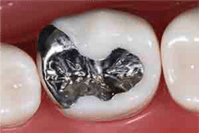

麻布十番の歯医者さんでシルバーインレーを詰めた状態のイメージ 麻布十番の歯医者さんでセラミックインレーを詰めた状態のイメージ 麻布十番の歯医者さんでジルコニアセラミックインレーを詰めた状態のイメージ

シルバーインレー セラミックインレー ジルコニアセラミックインレー

特徴 金属ですので、

強度がありますが、

アレルギーという問題と

目立つという問題があります。

値段 約4,000円 66,000円(税込) 55,000円(税込)

保証 保険診療のため保証なし 2年 2年

臭い 臭う 臭わない 臭わない

精度 悪い 良い 普通

アレルギー あり なし なし

強度 強い 弱い 非常に強い